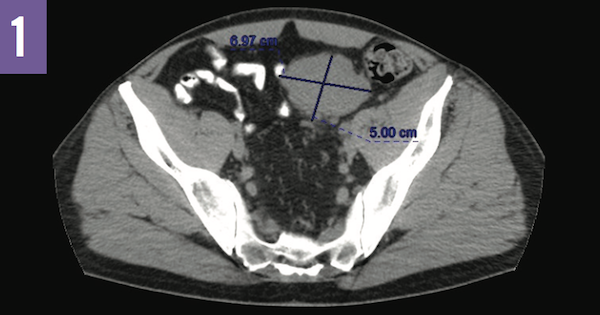

The patient was referred for a renal ultrasonography, which identified a mass in the left hemipelvis. Subsequent noncontrast computed tomography (CT) scans of the abdomen and pelvis revealed a 6.9 × 5.0-cm mass in the left external iliac chain with surrounding areas of nodularity, suggestive of lymphadenopathy or a primary mesenteric tumor. The patient then underwent a CT-guided left pelvic lymph node biopsy, the results of which were negative for malignancy.

Figure 1: Noncontrast CT scan of the pelvis showing a 6.9×5.0-cm mesenteric mass with surrounding nodularity.